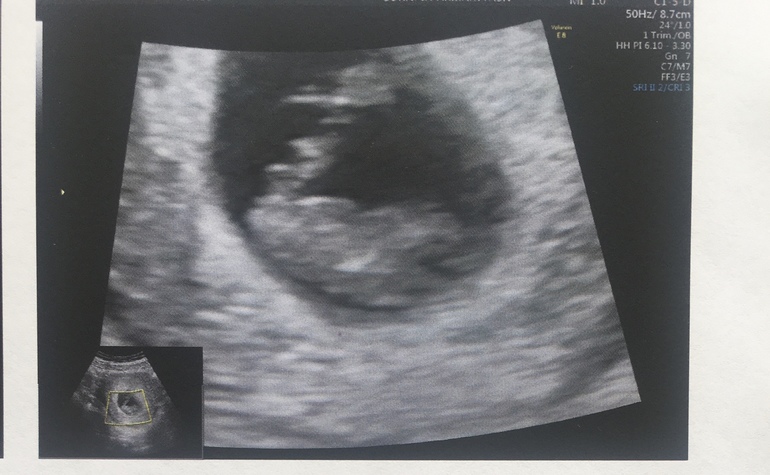

8 недель 3 дня. Первое УЗИ ❤️

По УЗИ все хорошо:

ЧСС - 176/мин

КТР - 20 мм ( на один день опережаем).

И фото на память